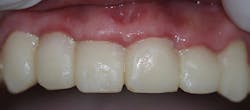

Upon his return three weeks later, the provisional was removed and the definitive laboratory-fabricated crowns were tried-in (figure 7). With excellent margins, this impression material speaks to the accuracy of capturing preparation detail, eliminating this potential concern and allowing the practitioner peace of mind.

Figure 7: Final crown try-in